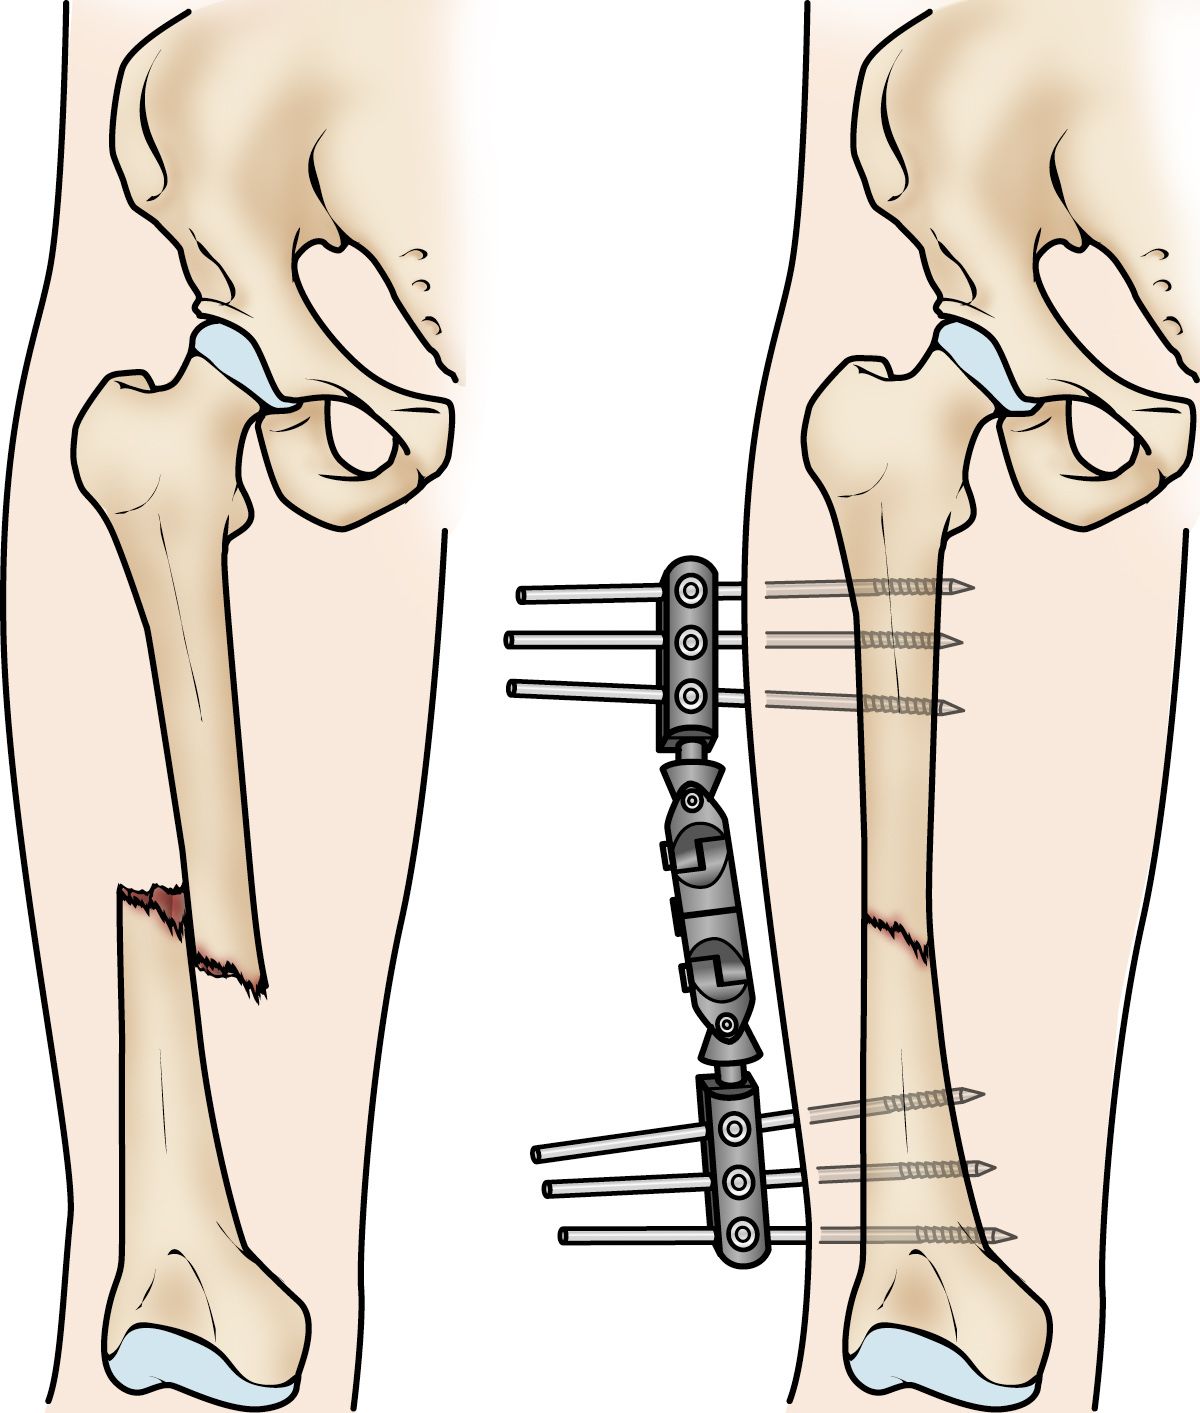

Fijación externa. En este tipo de operación, se colocan tornillos o sujetadores metálicos en el hueso por arriba y por debajo del sitio de la fractura. Los sujetadores y tornillos se ajustan a una barra fuera de la piel. Este dispositivo es un marco de estabilización que mantiene los huesos en la posición correcta.

La fijación externa suele ser un tratamiento temporal para las fracturas de fémur. Debido a su fácil aplicación, los fijadores externos suelen colocarse cuando el paciente tiene varias lesiones y aún no está listo para una cirugía más extensa para solucionar la fractura. Un fijador externo ofrece una buena estabilidad temporal hasta que el paciente esté lo suficientemente sano para la cirugía final. En algunos casos, el fijador externo se deja colocado hasta que el fémur se haya curado por completo, pero esto no es algo frecuente.

La fijación externa se suele usar para mantener los huesos unidos temporalmente cuando ha habido lesiones en la piel y los músculos.